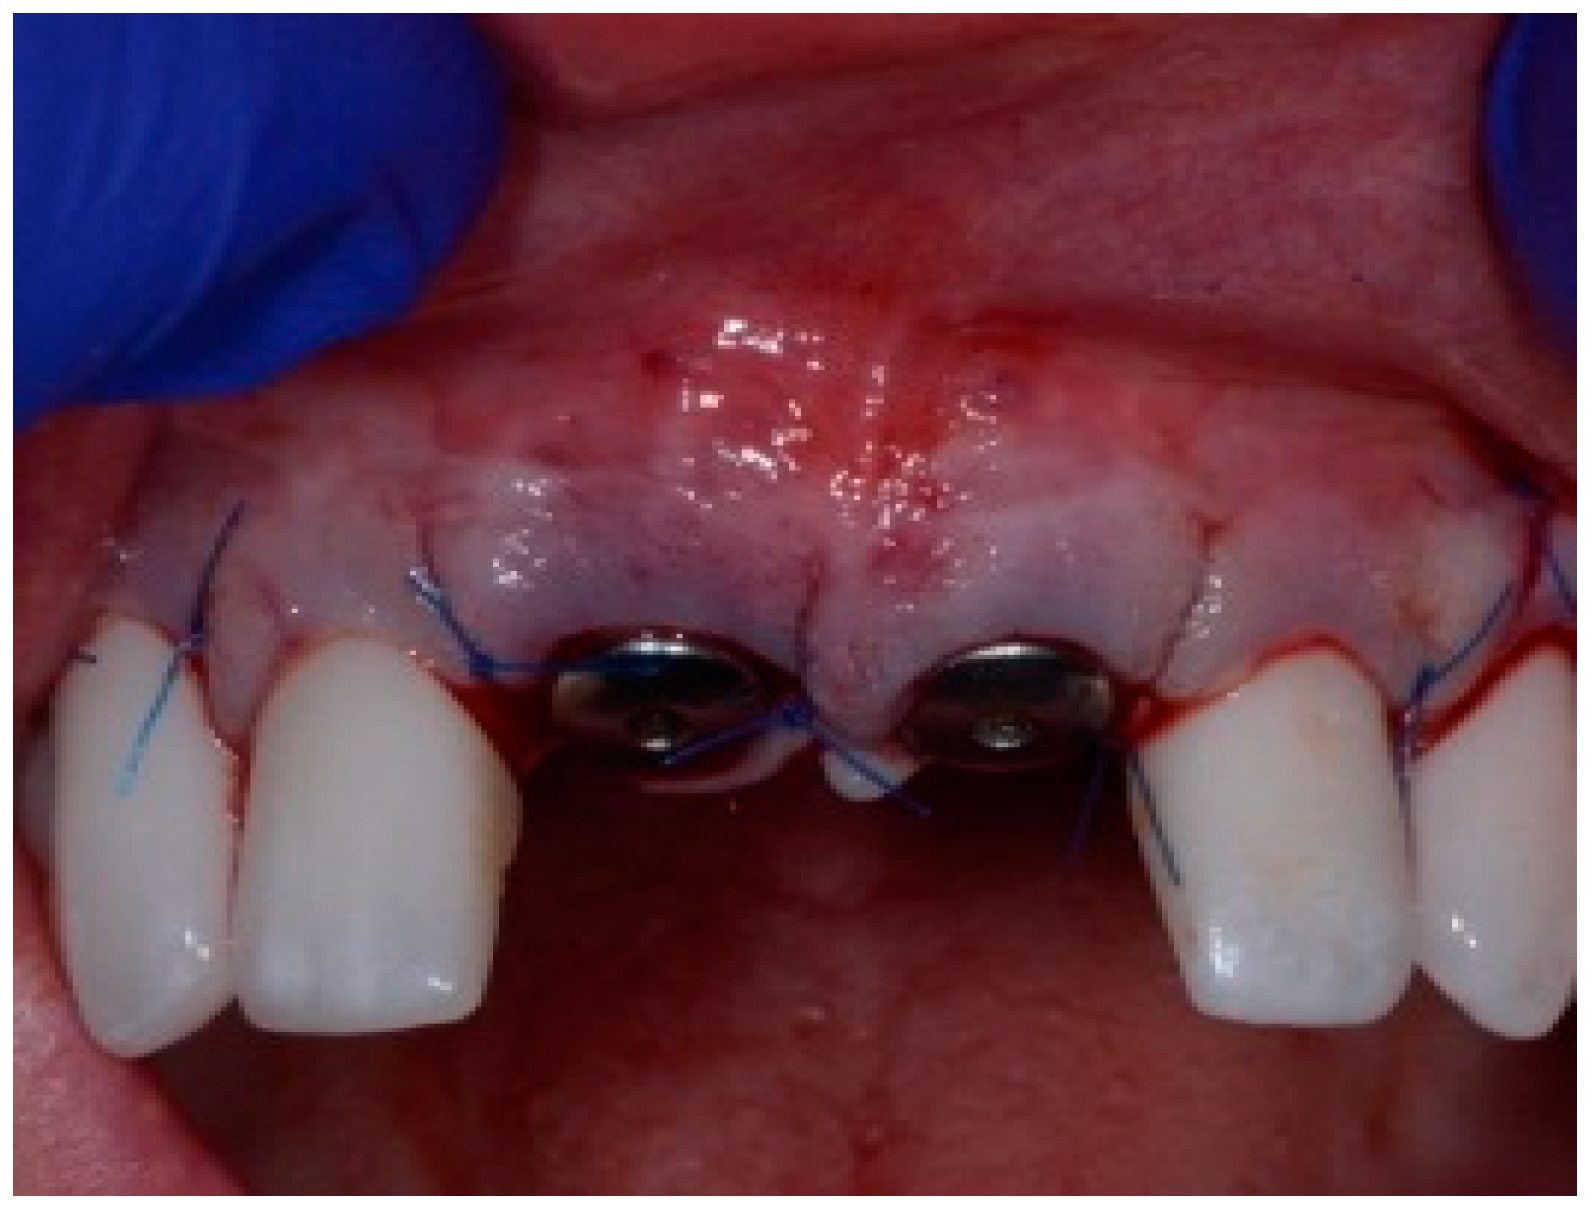

Before the graft and membrane is placed over the defect, a periosteal dissection must be performed to release flap tension to facilitate its coronal advancement and closure. The horizontal incision is made 1 mm deep into the periosteum, apical to the mucogingival junction, in a single plane along the length of the flap, connecting the two vertical releasing incisions. After the placement of this shallow incision, a micro-elevator is used to stretch within the incision line. This stretching not only releases the tension within the flap but also allows a more coronal advancement of the flap margin for eventual primary closure, minimizing postoperative incision line opening. This important step in flap management is performed before the placement of the graft material because the periosteal-releasing incision is associated with increased bleeding, which will complicate the graft, the membrane placement, and stabilization. A composite graft material consisting of allograft and xenograft in a 50/50 mix was placed in the gap between the implant and the socket wall over-contouring the facial wall defect (Figure 4). Two healing abutments were placed on the implants, followed by a bioabsorbable collagen membrane (Zmatrix, Osteogenics, Lubbock, TX 79424, USA) placed over the surgical area, which was closed with 5.0 polypropylene sutures (Figure 5). An Essex appliance, fabricated inhouse using a standard suck-down process, was inserted postsurgically. The implants were allowed to heal in a non-submerged environment for a period of 6 months.

Figure 4.

Clinical view post graphing.

Figure 5.

Clinical view of the final flap closure.